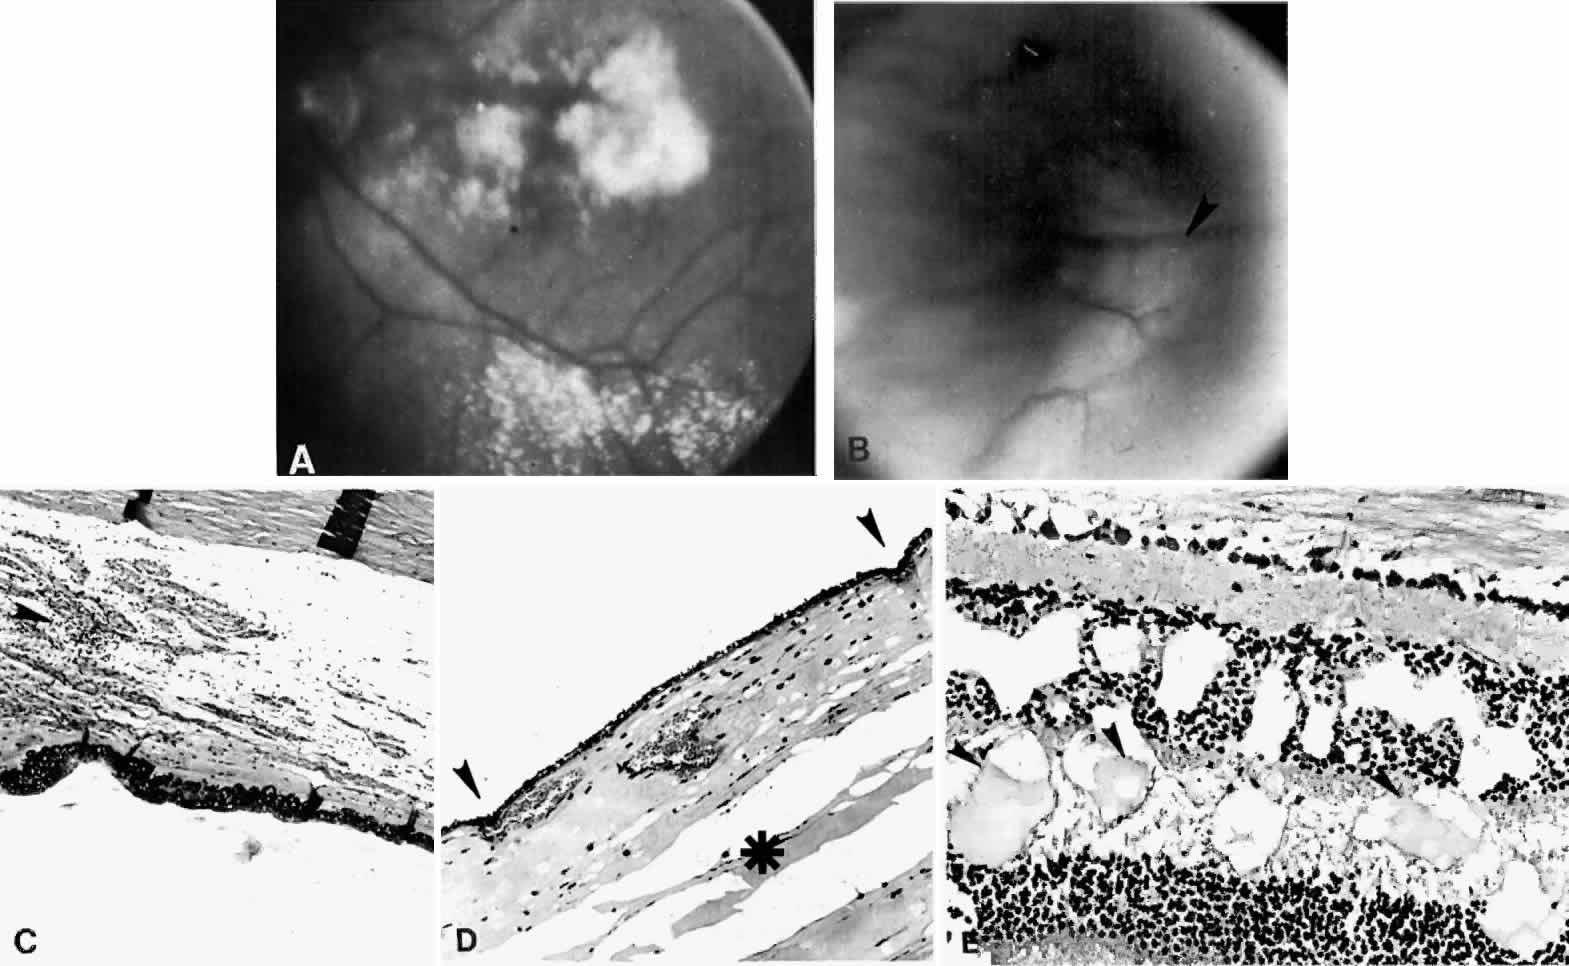

Fig. 15. A spontaneous ciliochoroidal effusion was mistaken for a malignant melanoma in a 61-year-old woman who presented with pain, blurred vision, keratitic precipitates, and aqueous cells and flare. A. Gross appearance of the ciliochoroidal effusion (large arrowheads). Small whitish inflammatory nodules are present in the choroid (small arrowheads). The apparent retinal detachment is artifact. B. An extensive ciliochoroidal effusion (asterisk) with a moderately intense chronic inflammatory cellular infiltration. (H & E, × 20). C. The choroid viewed posteriorly, showing occlusive granulomatous vasculitis (arrow) and an intense lymphocytic infiltration crowding the choriocapillaris. The retinal pigment epithelium is intact (H & E, × 290). D. Intense lymphocytic infiltration of choroid, inner scleral lamellae, and episclera (H & E, × 55). E. Diffuse scleritis viewed posteriorly, showing perineural lymphocytic infiltration in the episclera and within a scleral canal (arrowheads) (H & E, × 55).

Fig. 20. A 61-year-old man presented with a 10-day history of decreasing vision in the left eye.96 Examination disclosed a vision of hand motions, an irregularly shallow anterior chamber, closure of the angle, and an intraocular pressure of 45 mmHg. The ora serrata was visible without scleral depression. Ophthalmoscopic examination disclosed two large areas of solid-appearing lesions of the pars plana and anterior choroid (situated superonasally and inferotemporally), detachment of the retina, and a diffuse pigmentary disturbance, which was linear in some areas. Transscleral transillumination disclosed that areas of solid choroidal lesions lit up when viewed through the pupil. Radioactive phosphorus uptake was 16% at 1 hour, 18% at 24 hours, and 44% at 72 hours. The eye was enucleated because of the suspicion of a malignant melanoma. A. An extensive ciliochoroidal effusion (asterisks) showing mild diffuse and marked focal (arrowhead) infiltration of lymphocytes. The equatorial sclera is markedly thickened, and there is a large serous detachment of the retina (H & E, × 17). B. Edematous choroid with a large aggregate of lymphocytes (H & E, × 100). C. The equatorial area shows a thickened sclera, an edematous choroid with diffuse and marked focal aggregates of lymphocytes, localized area of retinal pigment epithelial hypertrophy and hyperplasia (arrowheads), slight folds in the retinal pigment epithelium and inner aspect of the choroid (arrows), and proteinaceous material (asterisk) in the subretinal space (H & E, × 40). D. A choroidal effusion with overlying proliferation of retinal pigment epithelium in nodular and linear configurations. Proteinaceous material is present in some areas in or beneath the retinal pigment epithelium (arrowheads) (H & E, × 180).

Histopathologically, there is a variable lymphocytic infiltrate in the ciliary body and choroid (see Figs. 19 and 20; Fig. 21).96